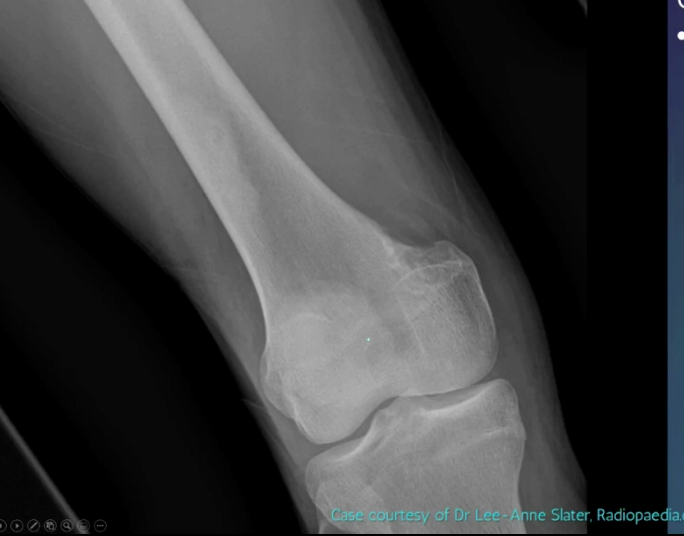

Segond fracture

Dr Subhan Iqbal◉ and Assoc Prof Frank Gaillard◉◈ et al.

Segond fracture is an avulsion fracture of the knee that involves the lateral aspect of the tibial plateau and is very frequently (~75% of cases) associated with disruption of the anterior cruciate ligament (ACL). On the frontal knee radiograph, it may be referred to as the lateral capsular sign.

The classical appearance of a Segond fracture is that of a curvilinear or elliptic bone fragment projected parallel to the lateral aspect of the tibial plateau. This has been referred to as the lateral capsular sign 1, which is best seen on the anteroposterior view of the knee.